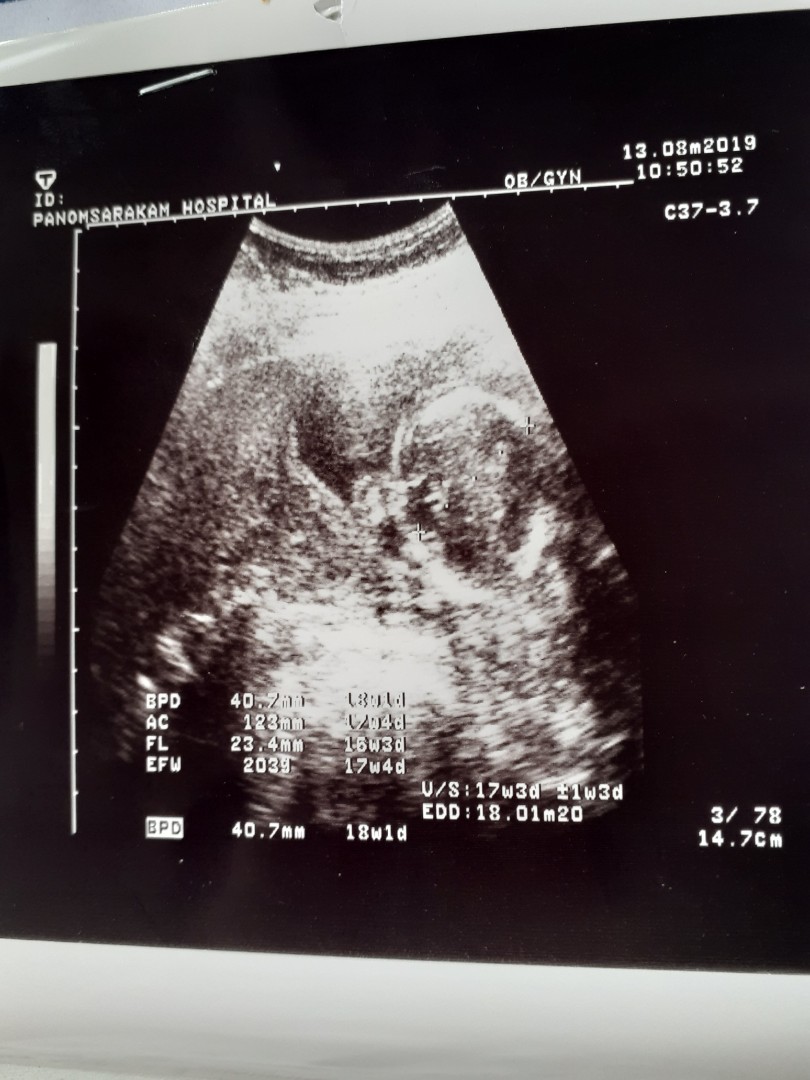

17weekจ้า